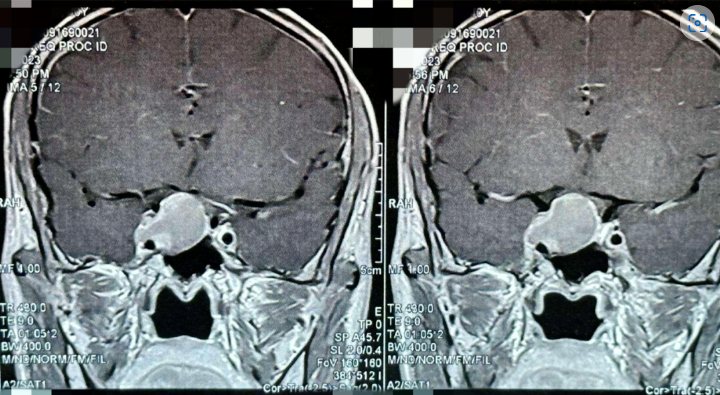

患者術前影像